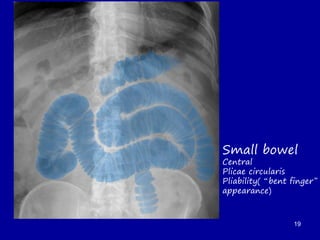

Small bowel

Central

Plicae circularis

Pliability(“bent finger”

appearance)

19